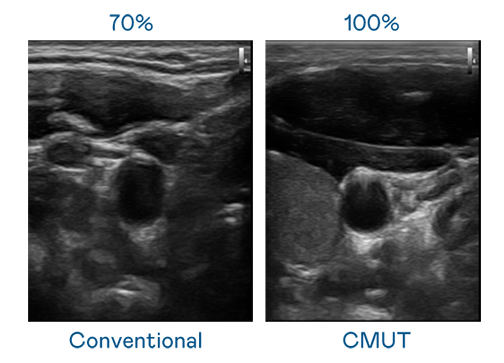

CMUT 技術是一種用電容式微機電元件來產生超音波訊號的技術。與傳統 PZT 壓電式技術相比,CMUT 頻寬增加 30%,更寬頻的超音波訊號讓影像解析度大幅提升,是實現高影像品質醫療超音波掃描、促進精準醫療發展的關鍵技術。

大頻寬帶來超清晰影像

超音波影像的解析度高低,首先取決於探頭能發出的訊號頻寬。4001百老汇 CMUT 可提供高清晰的超音波訊號,提供高頻寬、高靈敏度、影像紋理細節更高的超音波影像,協助醫護人員縮短影像判讀時間及利用精準的醫療影像進行診斷。